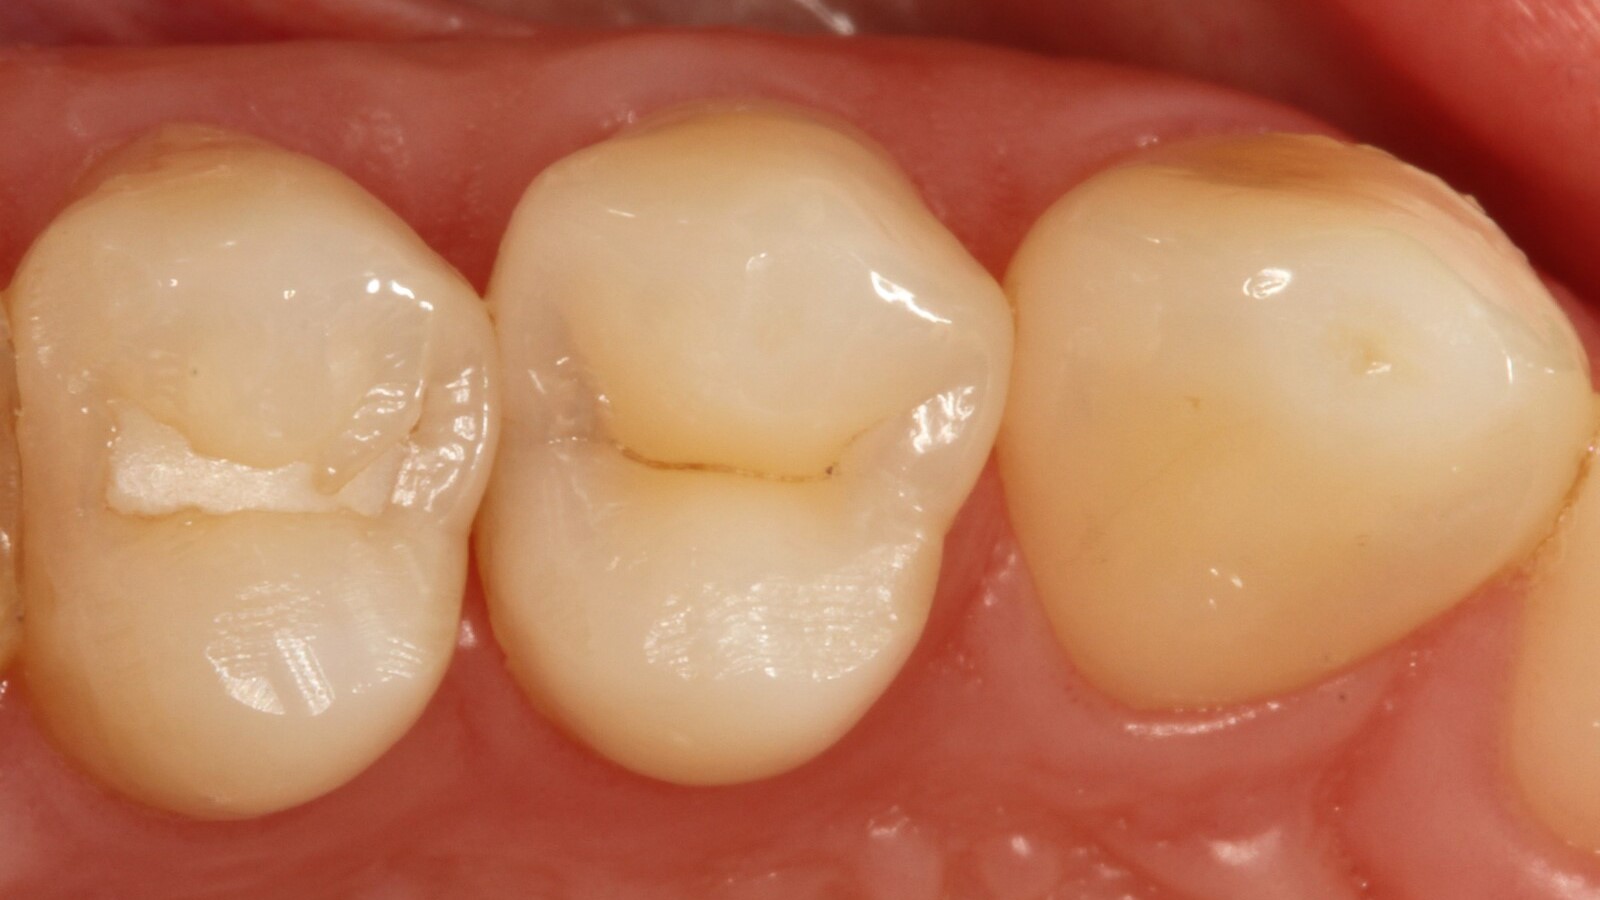

Professor Ernst first identified the hidden caries and opened the carious lesion to show the patient the problem (Fig. 1-2). He then excavated the caries, prepared the cavity and placed a sectional matrix (Fig. 3) before sealing the cavity with adhesive (Fig. 4). In a single step, he filled the cavity with Venus Bulk Flow ONE (Fig. 5). Once the restoration was completed, Prof. Ernst polished it (Fig. 6) and took a control radiograph, which also shows the excellent radiopacity of Venus Bulk Flow ONE (Fig. 7).